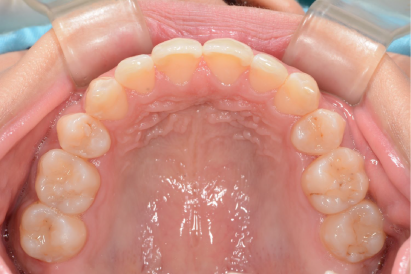

症例紹介

• 症例1

術前

*

術後

年代、性別

30代、女性

職業

会社役員

主訴

奥歯の詰め物が頻繫に取れる

部位

インビザラインによる全顎矯正と上下顎奥歯8本のセラミック治療

治療期間

1年6ヶ月

矯正費用

95万円

施術説明

患者は10年ほど前に矯正治療の既往がありました。歯並び自体は綺麗になったものの、矯正後に奥歯の詰め物が頻繁に外れて虫歯になり、総合的な治療を希望して来院されました。診察の結果、矯正治療をしているにも関わらず、前歯が噛んでいないので奥歯に過剰な咬合負荷がかかっていることがわかりました。そのため、前歯を咬合させ、奥歯が干渉しないように再度の矯正と奥歯の修復治療が必要と判断しました。治療後には、審美的にも機能的にも満足して頂き、問題なく生活できるようになりました。このような治療は矯正専門医でなくては不可能です。歯のトラブルと歯並びが複合する問題は、複数の専門医が所属する医院を受診して下さい。

副作用・リスク

なし